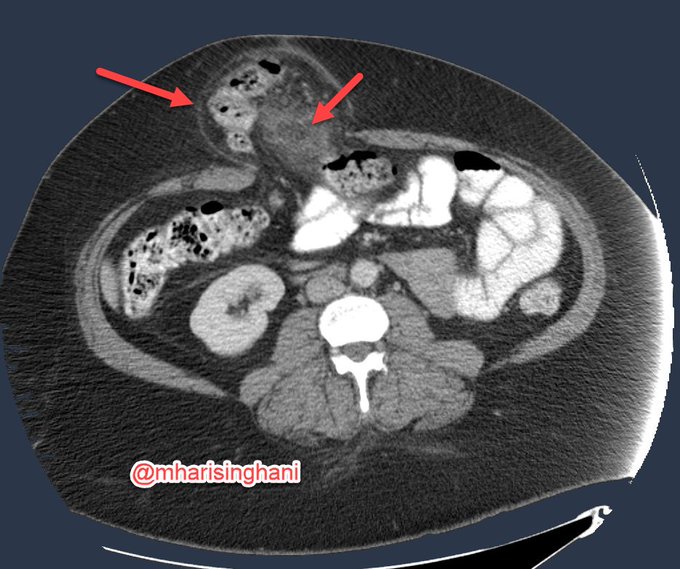

Is that aneurysmal dilatation due to lymphoma; not always; this was metastatic RCC to bowel (left kidney out for clear cell RCC)